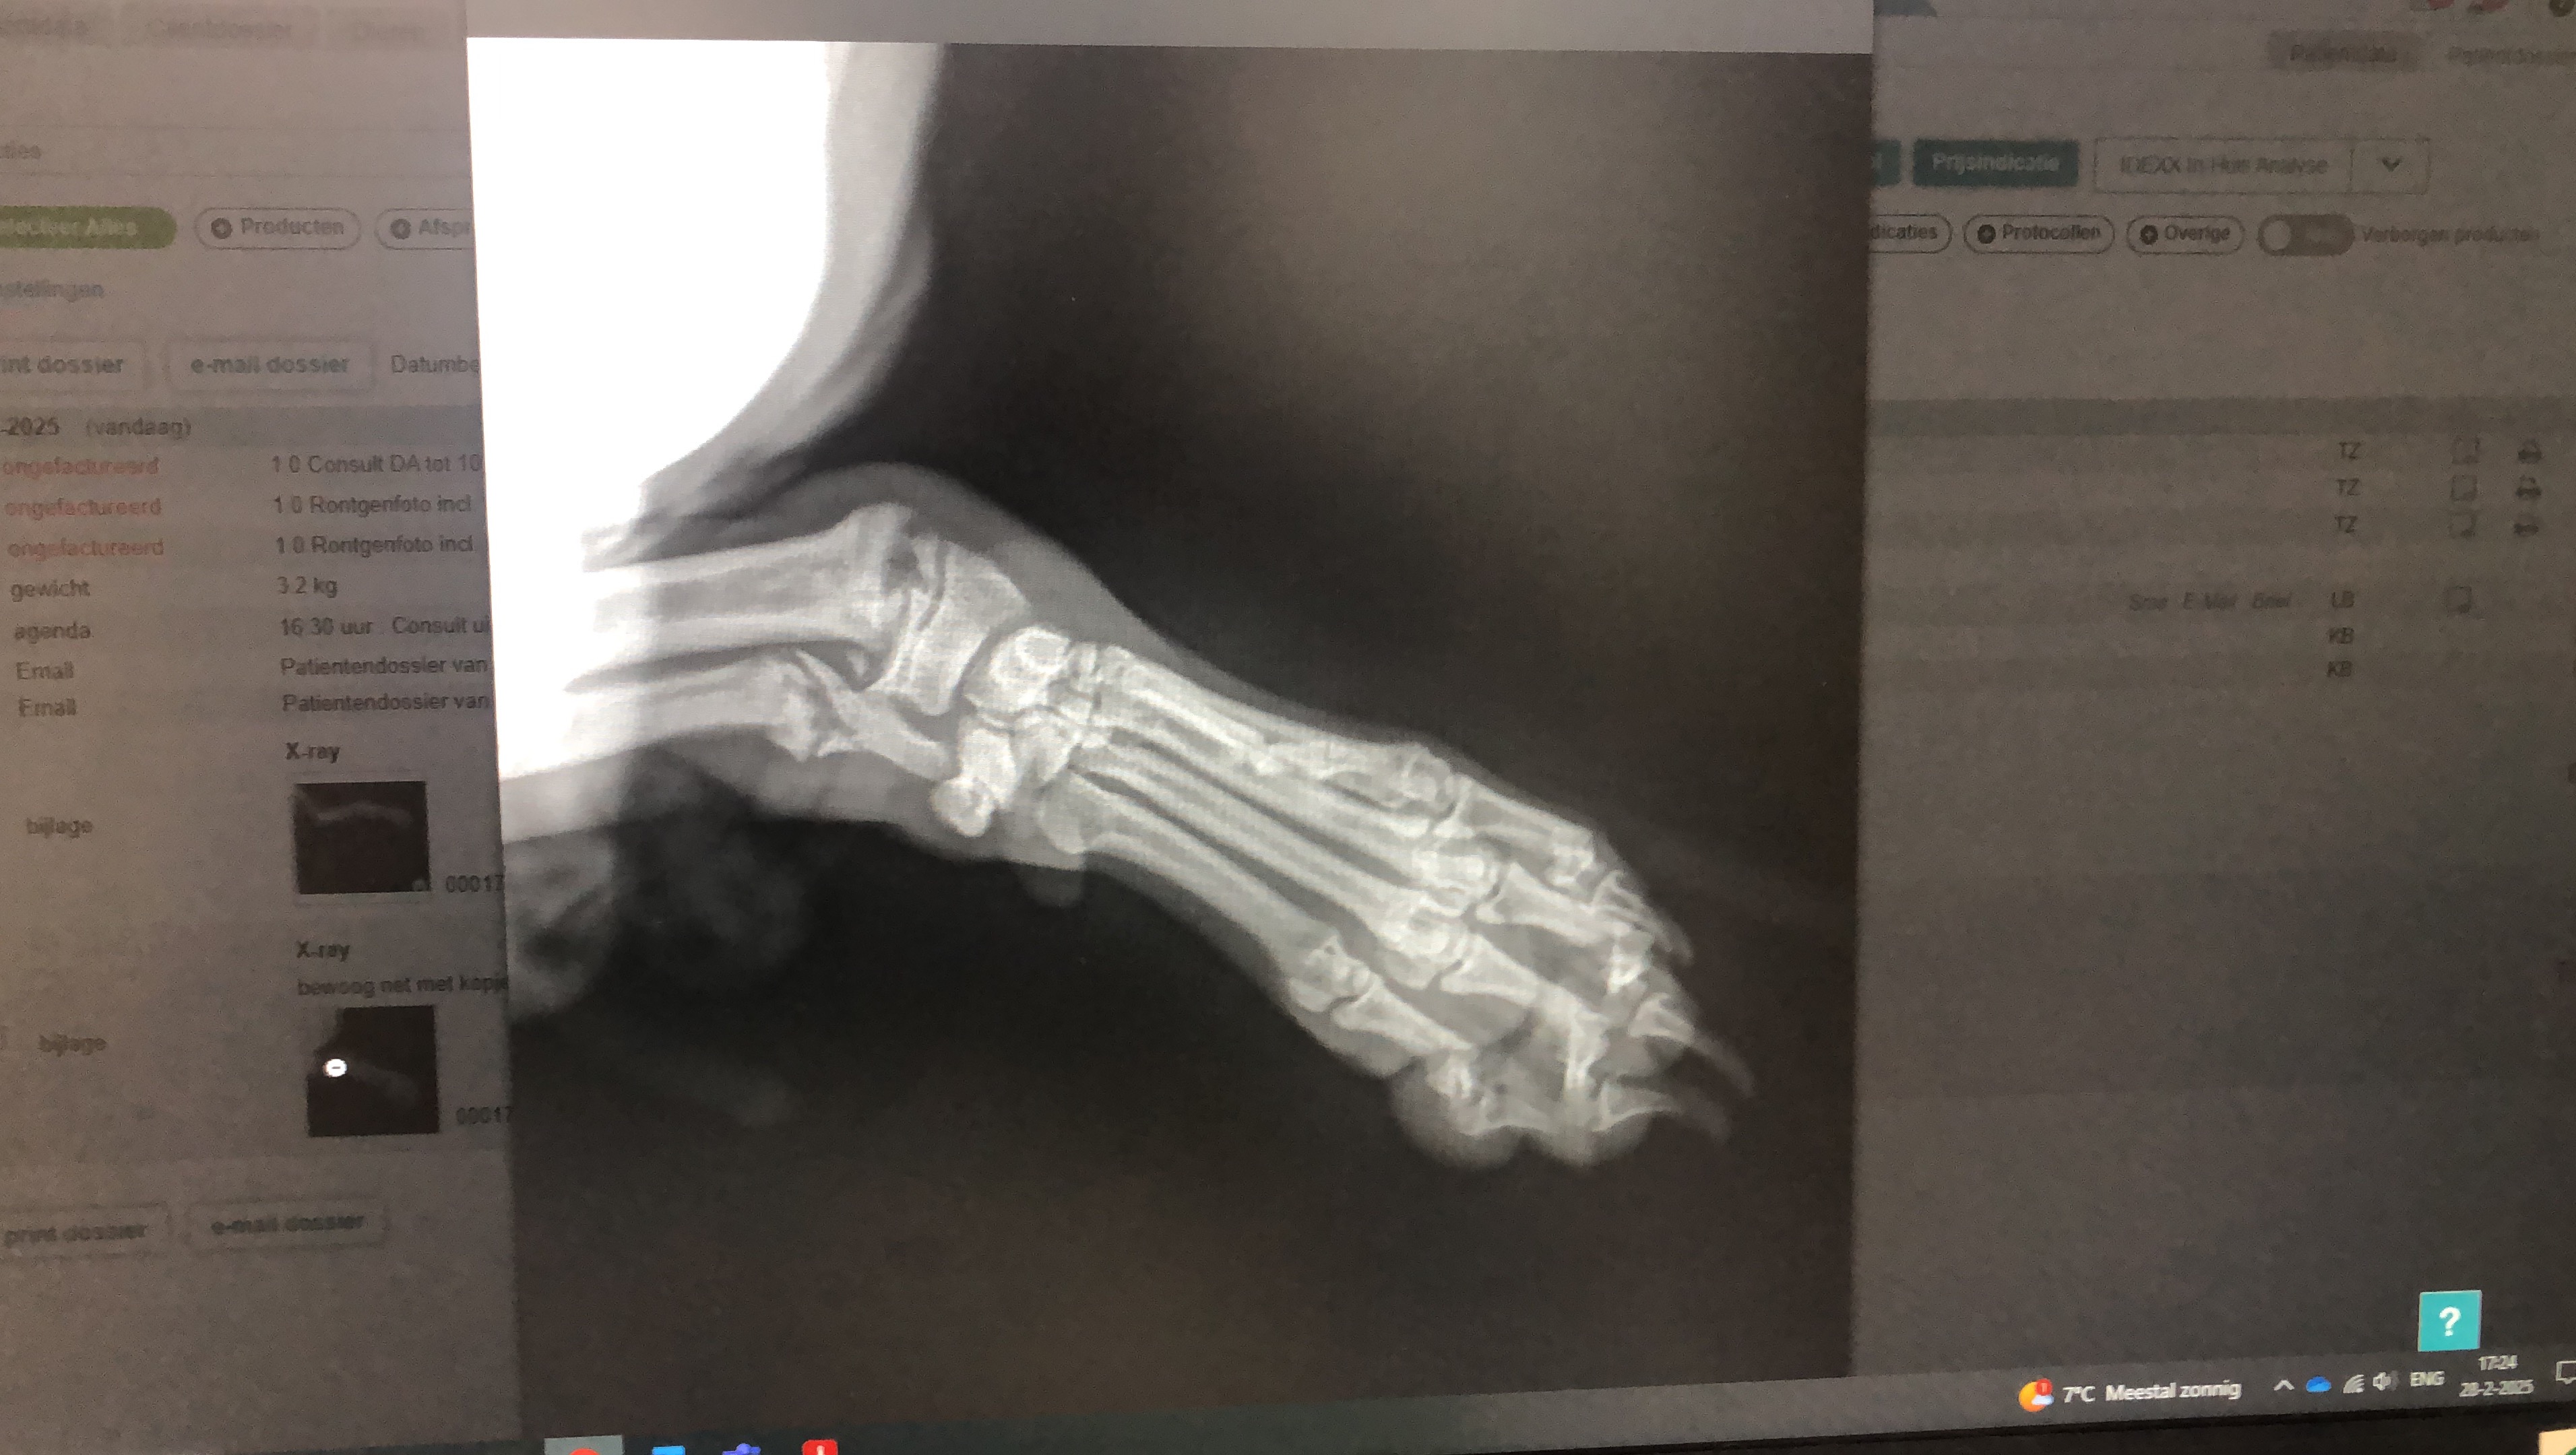

Mijn naam is Maureen. Grote dierenliefhebber. Graag heb ik financiële hulp nodig voor een eenzame vrouw en haar hondje Milo. Woensdag 26-02-2025 is Milo van de bank gevallen en schreeuwde het uit van de pijn. Donderdag had ik contact met mevrouw en ben ik samen met mijn collega Cindy vanuit Heerlen naar Papendrecht gereden.

Helaas is zijn pootje niet meer te redden. Milo is 5 maanden.

Inmiddels is Milo geopereerd en zijn voorpoot geamputeerd.